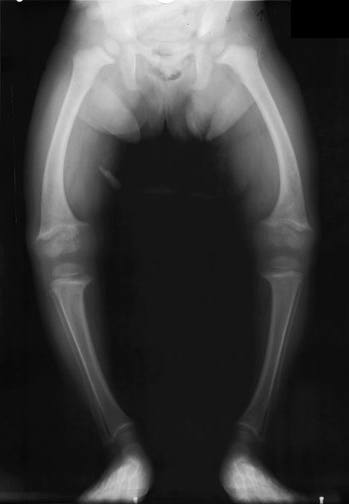

Vitamin D is found in a variety of foods particularly fish. Vitamin D helps to bind the calcium found in milk to form strong bones. Unfortunately this is becoming more common again. Common signs are bowed legs and arms as the bones do not contain enough calcium.

Here again x rays help to demonstrate this clearly. The whiter the image the more the x rays are blocked so the denser the bone. the first x ray on the left is of a normal set of legs.

This x ray shows the legs of a person suffering from Rickets. As you can see the image is much more faded and the bone walls are much thinner. as a result this person is more likely to break bones whereas a normal person might just bruise themselves.

In the second half of the 20th century rickets was thought to have been consigned to the history books but at the beginning of the 21st century it has made a comeback. A few years ago a child died of rickets here in the UK.